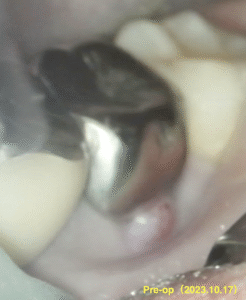

過去の治療の経過観察。

治療から1年が経過していた。

術前のSinus tract, 打診痛は消失した。